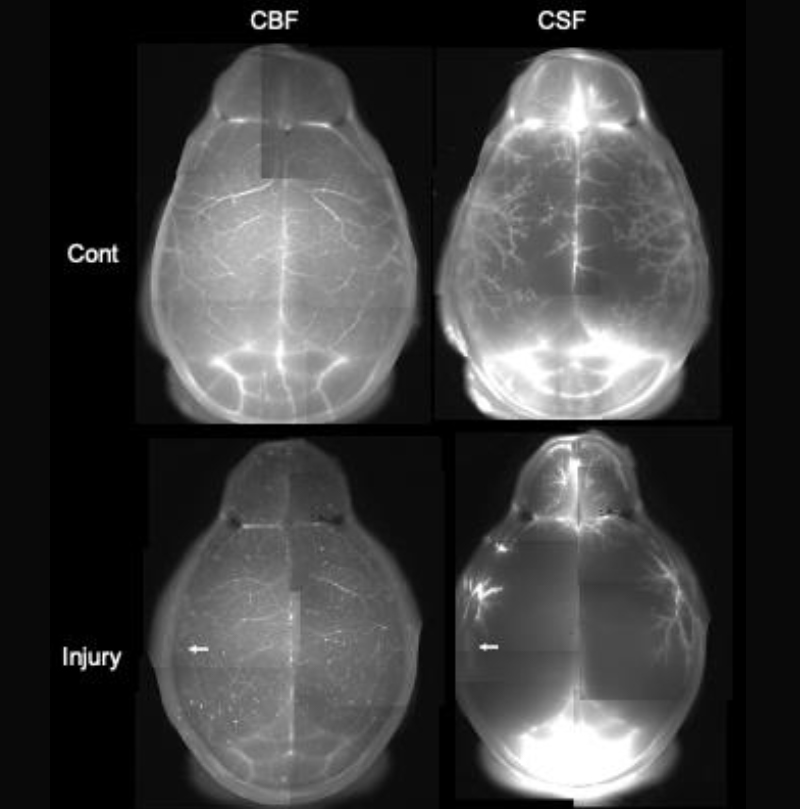

(b) 光傷害マウスにおける脳血流(CBF)と脳脊髄液の分布

私達の体は血管系とリンパ系という2つの水循環を持っています。しかし、脳はリンパ系を持たず、その代わりに脳脊髄液(Cerebrospinal fluid, CSF)とアストロサイトの水チャネル(AQP4)という、独自の水循環を発達させています。CSFがどのように流れているかは、未だによく分かっていませんが、脳の血管は周囲にスペースを持ち、CSFはこのスペースを流れて脳組織内外を循環するという Glymphatic systemが提唱されています(図a)。また、AQP4はアストロサイトと血管の境界に高い密度で局在し、AQP4欠損マウスはGlymphatic systemの循環が著しく低下することが分かっています。このため、上述のAQP4依存的なアデノシン放出は、血管から脳内に水が流れ込む過程で活性化されると考えられます。私達は光傷害マウスのCSF循環を調べるため、脳血流(Cerebral blood flow, CBF)とCSFに異なる蛍光色素を注入し、二重標識しました(図b)。その結果、正常マウス(Cont)では脳表面の血管に沿って分布していたCSFが、矢印で示した部分に光傷害を作製したマウスでは、脳全体で減少していることが分かりました。おそらく脳は一部が壊れると、アストロサイトの活性化などによりAQP4を介した水流入が減少し、脳全体のCSF循環が悪化すると考えられます。この結果は、交通事故やスポーツ事故による頭部打撲が、脳を局所的に破壊すると、脳機能が全般的に低下したり、うつ病などの精神疾患を発症させることと関係しているかもしれません。私達は局所的な脳傷害が、 CSF循環と先述のAQP4依存的なアデノシン放出を脳全体で変調させ、脳機能に様々な影響を与える可能性を、2光子ホログラフィック顕微鏡を用いて検討しています。これにより脳の活動が水の循環により結び付けられている実態が明らかになれば、脳の機能と疾患を解明する新しい切り口になると期待されます。